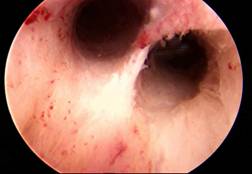

Normal Laproscopy